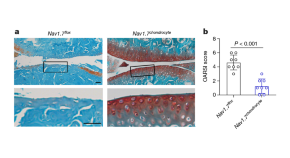

RNA-sequencing analysis of cells in the human cortex enabled identification of diverse cell types, revealing well-conserved architecture and homologous cell types as well as extensive differences when compared with datasets covering the analogous region of the mouse brain.

Whether cell types in the brain have been conserved during evolution is not clear. A comparison of the molecular recipes that define brain cell types in humans and mice reveals similarities and differences between species.

• Matthew G. Keefe

•  & Tomasz J. Nowakowski